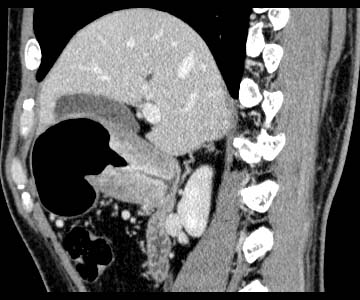

Gastric cancer / Borr.II

Sagittal MPR

Data acquired & processed by R. Kato M.D.